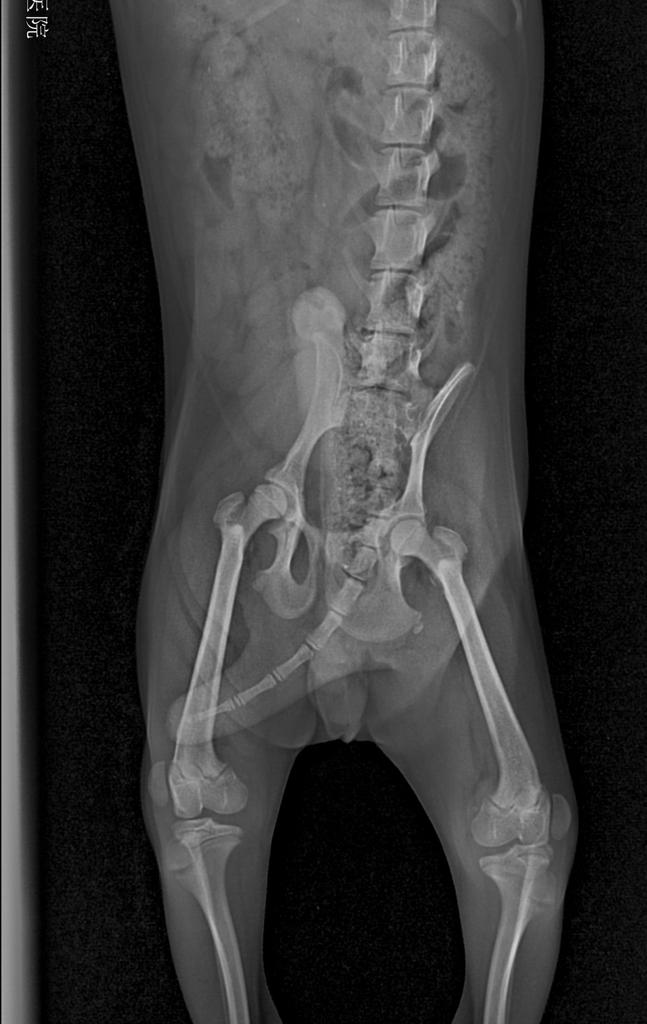

根据主人的症状描述,没有任何外伤和刺激狗狗突然后腿不敢着地,然后跑起来会自行恢复,配合宠物医生的髌骨部位触诊,以及照射x光后,即可确诊。

狗狗髌骨脱位最坏的后果有多严重,狗狗髌骨脱位临床症状